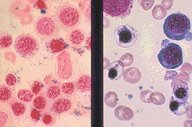

Myelodysplasia, Refractory Anemia with ring

sideroblasts (RARB)(Lft)/RARB(Rt) iron-stain

Myelodisplasia. (1) Marked erythroid dyspoiesis

is seen in this high-dry view. Diagnosis was

Refractory anemia with ring sideroblasts (RARB).

(2) An iron-stain in the same patient showing

perinuclear rings of iron-laden mitochondria.